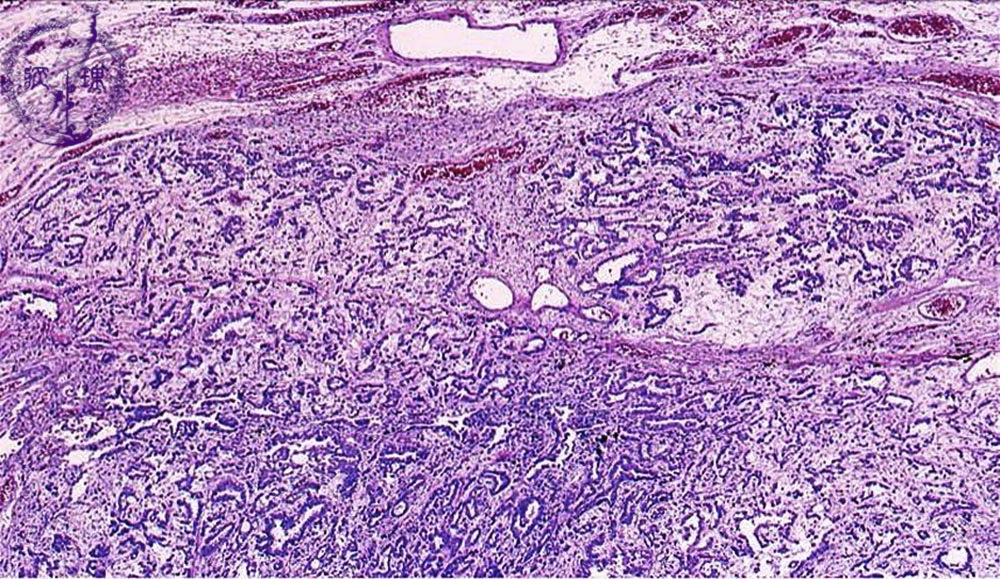

Microscopic view (HE stain, low power view): This mesothelioma has a tubulo-papillary structure with abundant stroma.